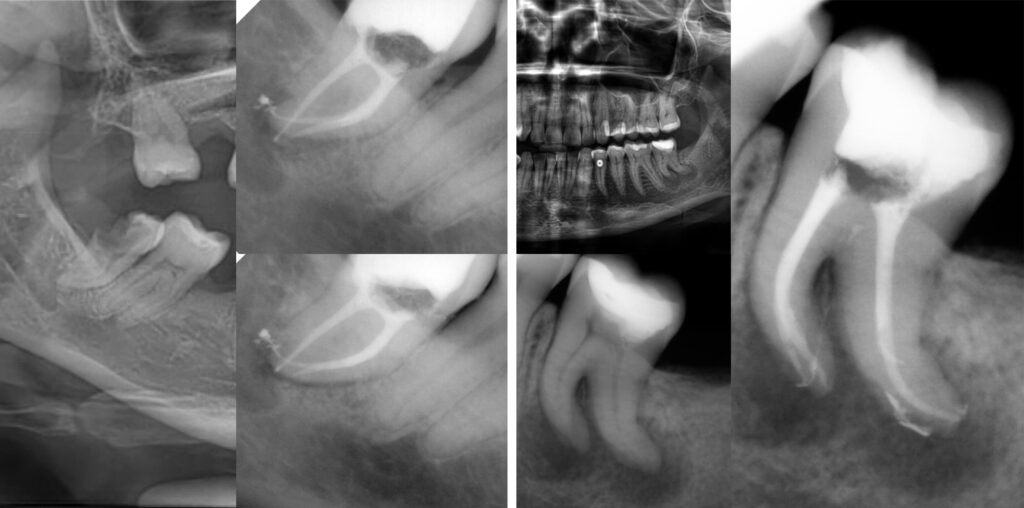

Например случаят с дванадесетгодишно момче с „dens in dente” беше предизвикателство за мен по това време. Довършвах магистърската си степен и случаят беше много по-труден от обикновено. Представляваше морфология тип II (според класификацията на Oehlers) с комуникация – което експоненциално увеличаваше трудността и като добавка – напълно отворен апекс. Планирах апексификация с MTA и, за да имам достъп до целият апекс трябваше да увелича апикалния форамен на инвагинация за пълно запечатване на целия апекс. Следващата стъпка беше обтурация на инвагинацията, също с MTA.